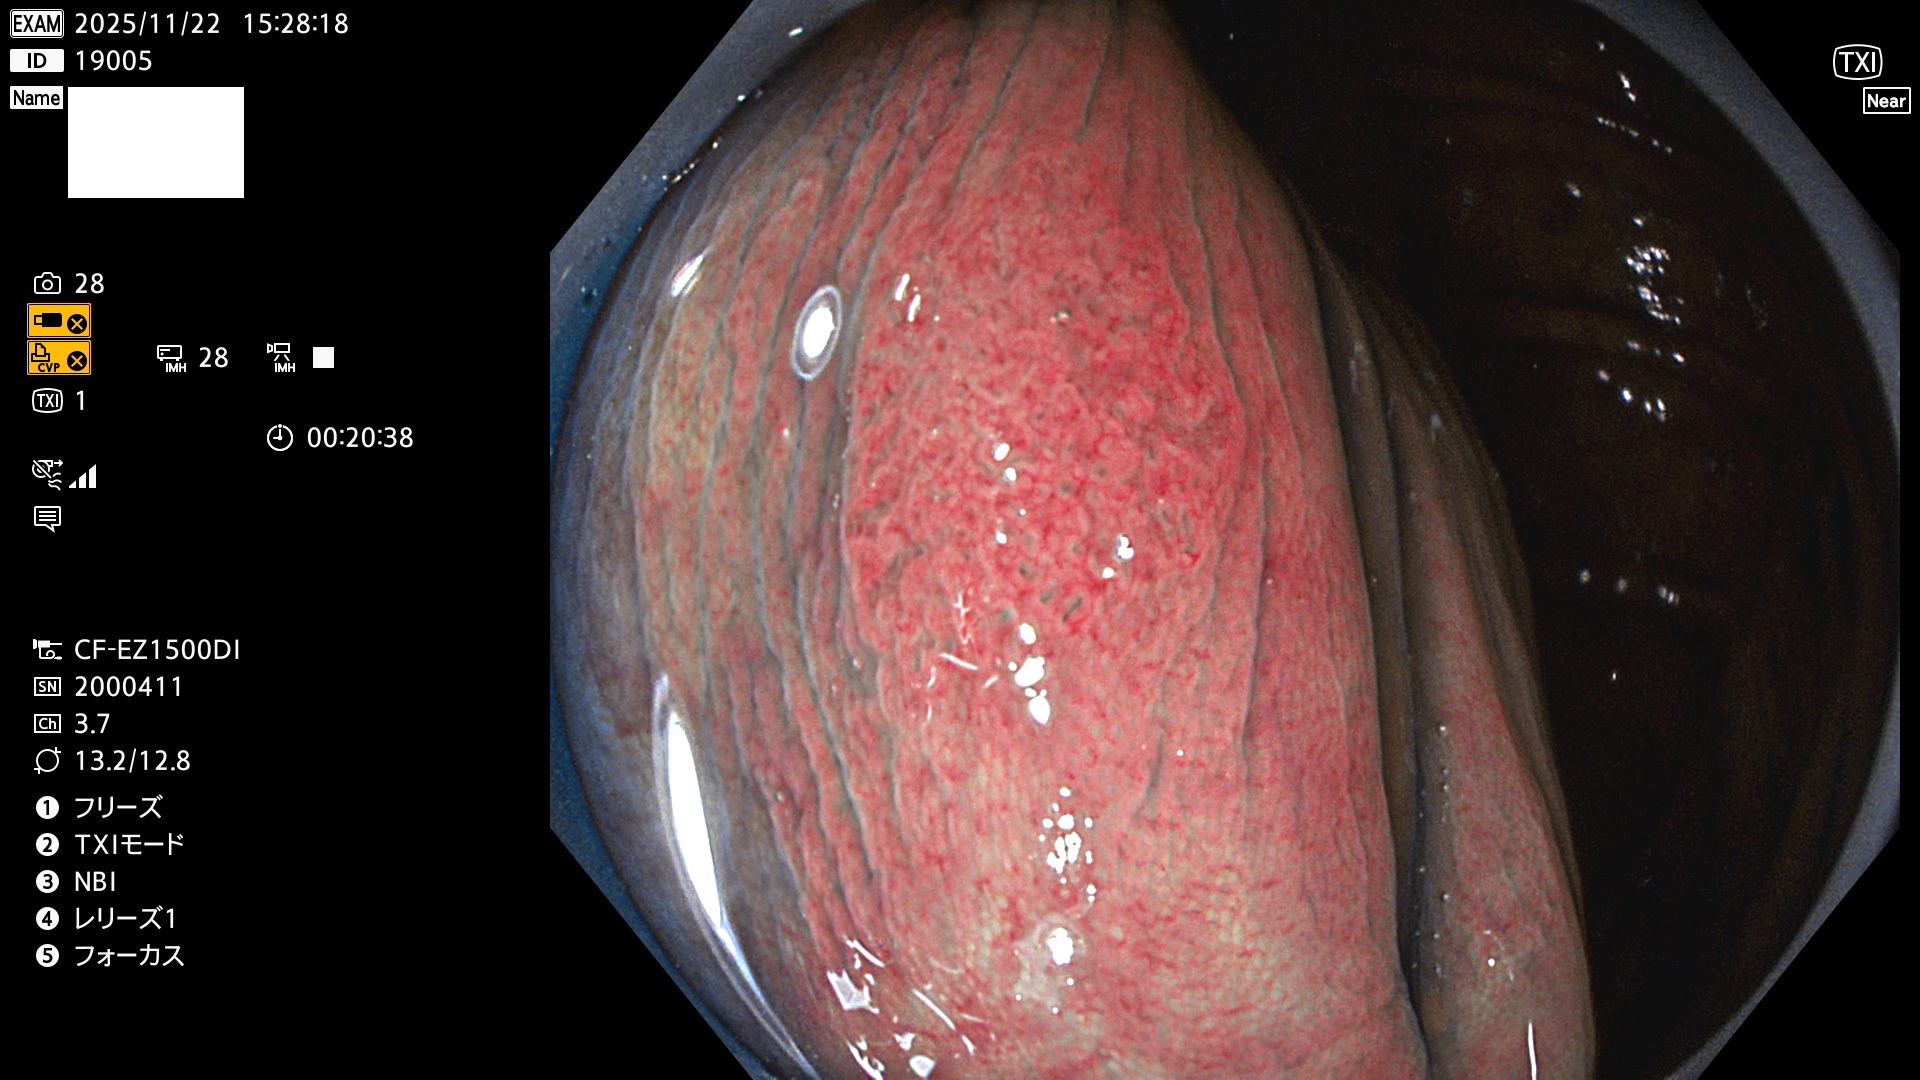

完全に平坦な物をUb、陥凹している物をUcと呼びます。Ubは認識が困難で、Ucはびらん(炎症)と紛らわしいために見落とされやすく、「内視鏡後・大腸癌」の原因になります。

専門的)Uc=De Novo癌? 内視鏡の解像度が低かった時代、このような説もありました。しかし今日の高精度内視鏡では良性の微小なUc型腺腫(APC遺伝子異常の腺腫)が日常的に見つかります。Ucこそが多段階発癌(Adenoma-Carcinoma Sequence)のMain Routeです。

毎週の検査(木・金・土・日)に発見されたUbとUc型・腺腫を、その週の日曜の夜にUPし1週間、提示します。

2025年11月20日〜11月23日の4日間(40件)8個 (Uc_ADR=8個/40人=20%)